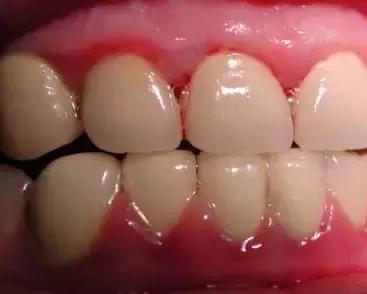

虽然起初没有任何的不适症状,但是会使牙龈由健康慢慢变为炎症状态:充血红肿、由坚韧的质地慢慢变得很脆,一旦受到刷牙和咀嚼时的机械摩擦就极易出血。

牙齿与牙龈缝处发黑一碰就出血,远离牙龈出血的一点小科普